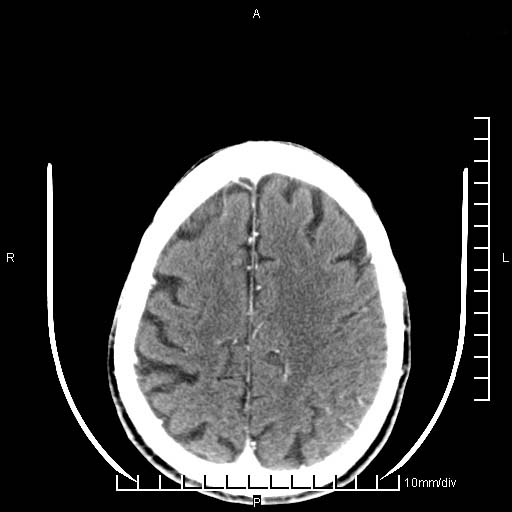

临床以双下肢浮肿,疼痛收治,无明显神经系统症状,既往无梗塞,出血病史。左颞叶见低密度灶,考虑什么?

考虑左侧颞叶脑软化灶。

无强化 无占位 软化灶吧

无强化、 无占位、局部脑沟增宽, 软化灶吧。